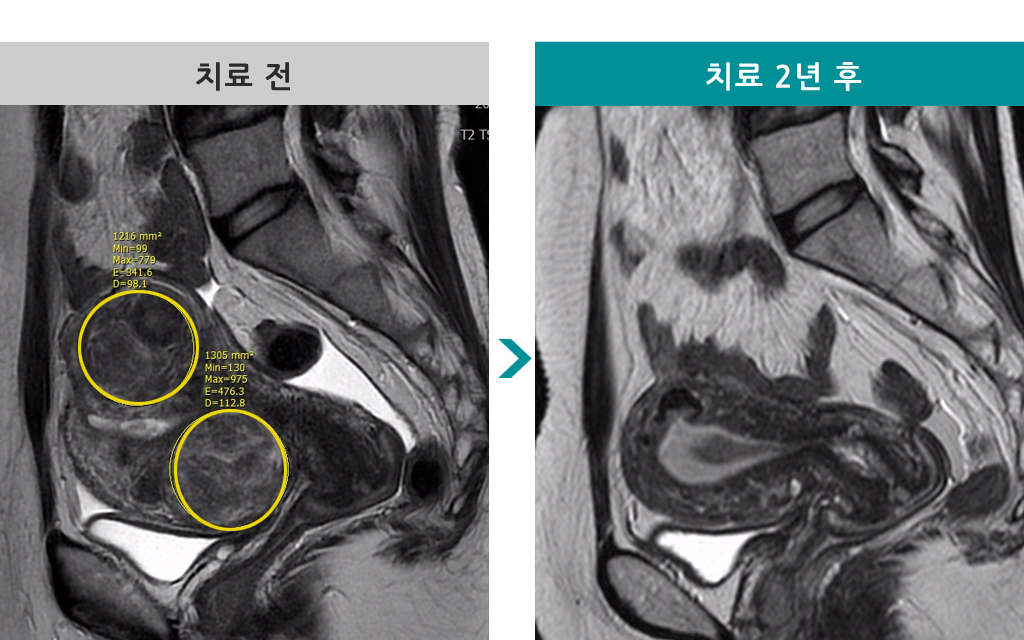

49세 [자궁근종 색전술] 전후 MRI사진 비교 - 거대근종